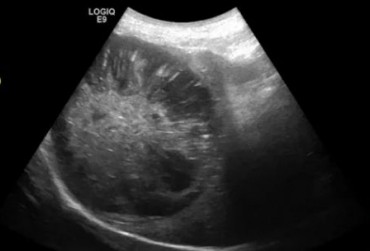

Torbiel pierwotna jest rzadką wadą rozwojową występującą u człowieka, psa, kota i konia. W niniejszym artykule opisano przypadek torbieli pierwotnej jelita prostego u dziewięcioletniego kota rasy Manx, u którego występowały przewlekłe zatwardzenia. W badaniu rektalnym i radiograficznie stwierdzono obecność miękkiego guza dogrzbietowo i bocznie od jelita grubego. Badaniem ultrasonograficznym i w tomografii komputerowej uwidoczniono dobrze odgraniczoną, cienkościenną torbiel, częściowo zamykającą światło kanału miednicy. Torbiel usunięto chirurgicznie z dojścia okołoodbytowego. Nie stwierdzono połączenia torbieli ze ścianą prostnicy. Badanie histopatologiczne potwierdziło postawione podejrzenie torbieli pierwotnej. Po wykonanym zabiegu objawy kliniczne całkowicie ustąpiły.